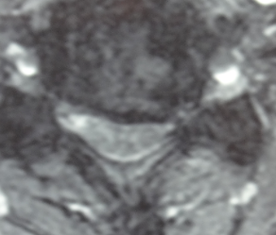

頚椎捻挫で12級13号の認定を受けた画像

この横断画像でわかりますが、C5/6、6/7の左優位の椎間板の膨隆により脊髄及び左神経根の圧排所見が得られています。

左前腕から第2乃至4指の痺れ等の症状を訴え、

左スパーリング・ジャクソンテスト陽性、

左握力低下・左腕徒手筋力テストいずれも4

上腕三頭筋腱反射低下

との神経学的異常所見が得られた結果、12級13号の認定を受けました。

上記C5/6の横断画像です。

左優位の椎間板の膨隆が認められ、脊髄と左神経根の圧排を認めます。